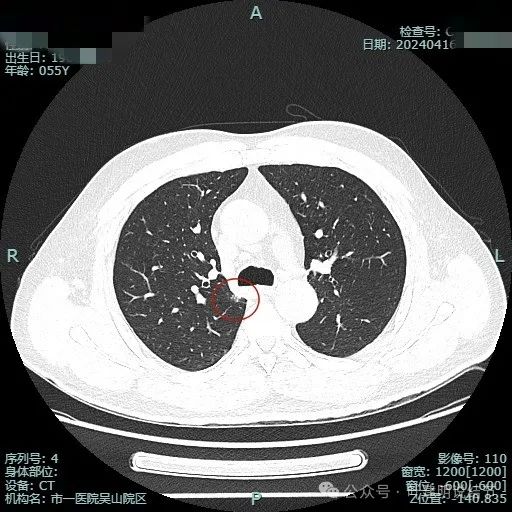

我们先来看2024年4月的病灶影像:

病灶出现,位于右上叶靠近肺门侧,此层显得像磨玻璃密度,轮廓较清。

其实应该实性密度的,前面层面应该是较为边缘部位的关系。病灶表面有点毛糙。